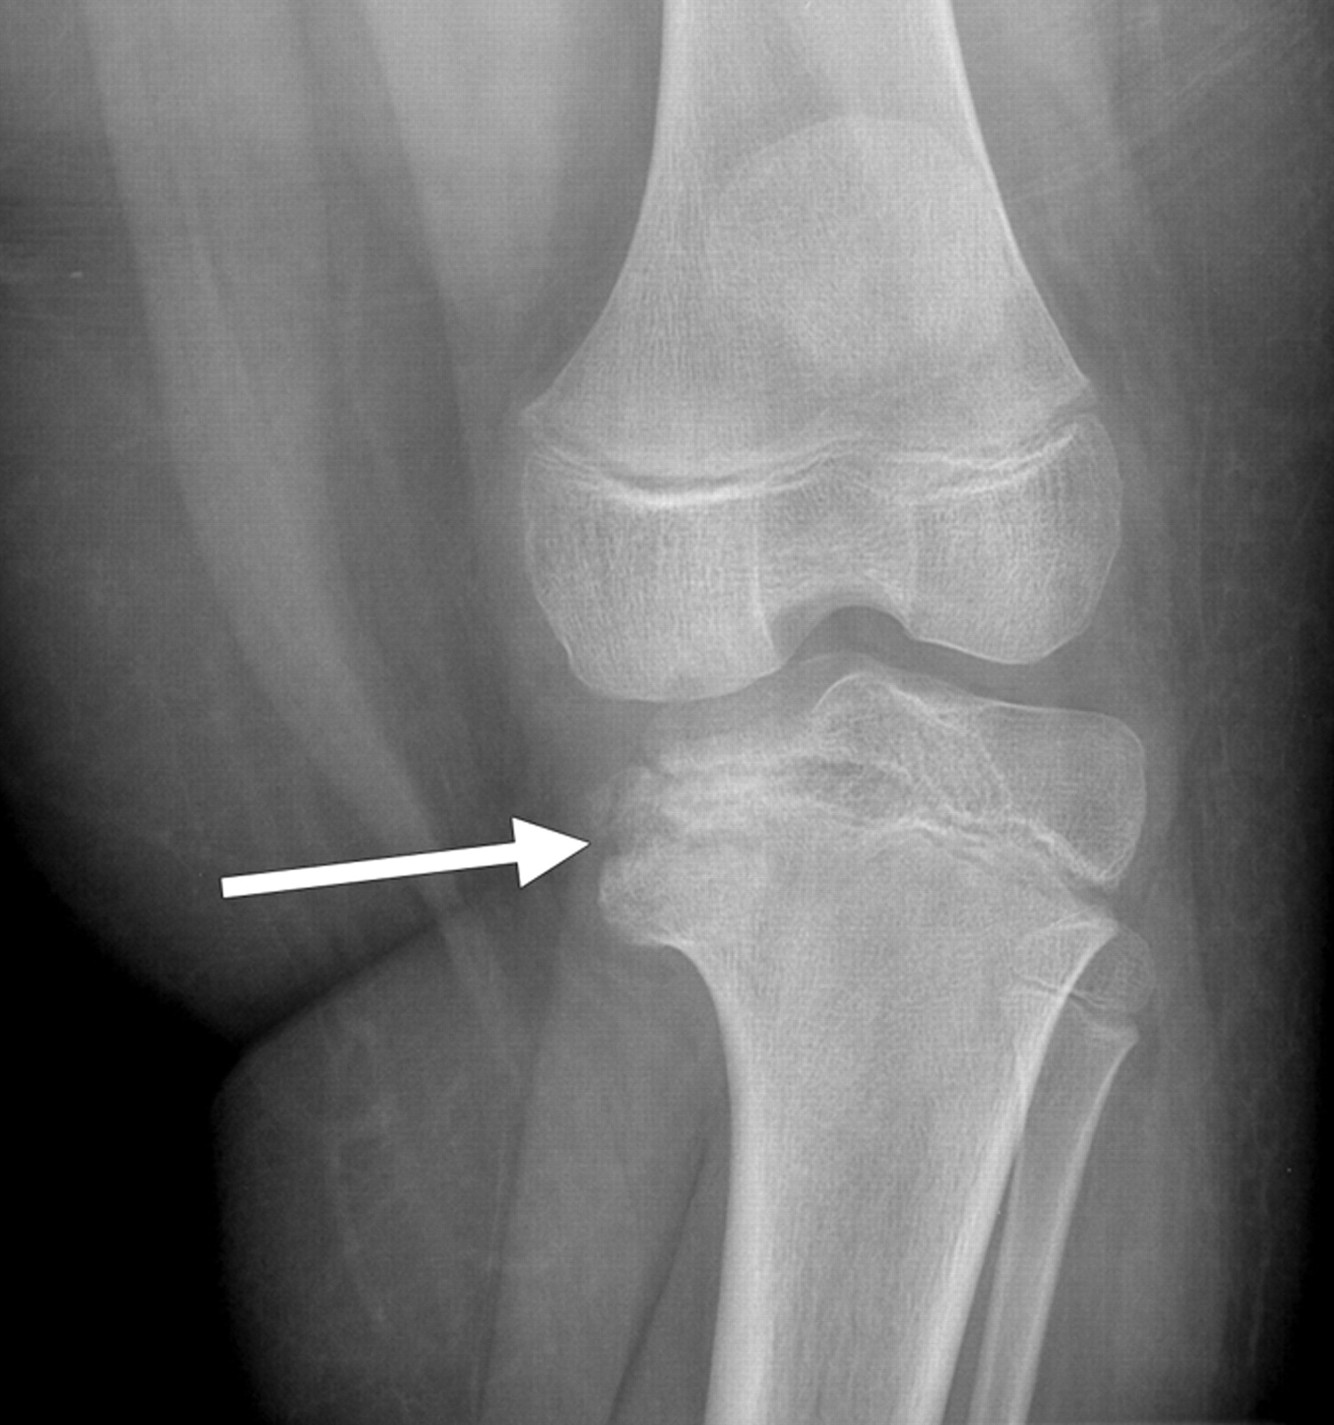

Large subchondral cysts without other degenerative changes

Large subchondral cysts, without other destructive changes, are suggestive of pigmented villonodular synovitis.

The presence of an (hemorrhagic) effusion supports this diagnosis.